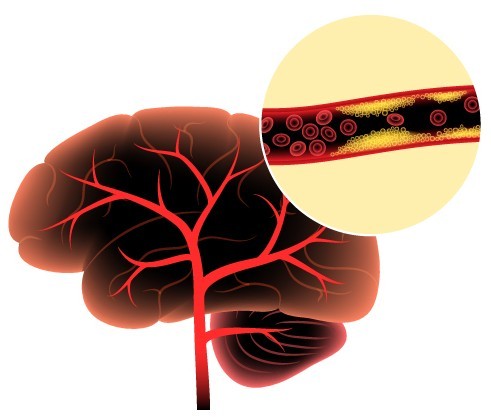

이는 뇌 후두엽의 혈류 이상으로 인한 증상일 수 있습니다.

이는 뇌의 특정 부위로 가는 혈류가 일시적으로 차단된 결과입니다.8. 삼키기 어려움(연하 곤란)

뇌졸중 치료의 황금 시간대는 증상 발생 후 3시간 이내입니다. - 미니중풍(TIA)도 반드시 검진을 받아야 하며,

고혈압, 당뇨, 고지혈증, 흡연, 비만, 스트레스는 주요 위험요소입니다.